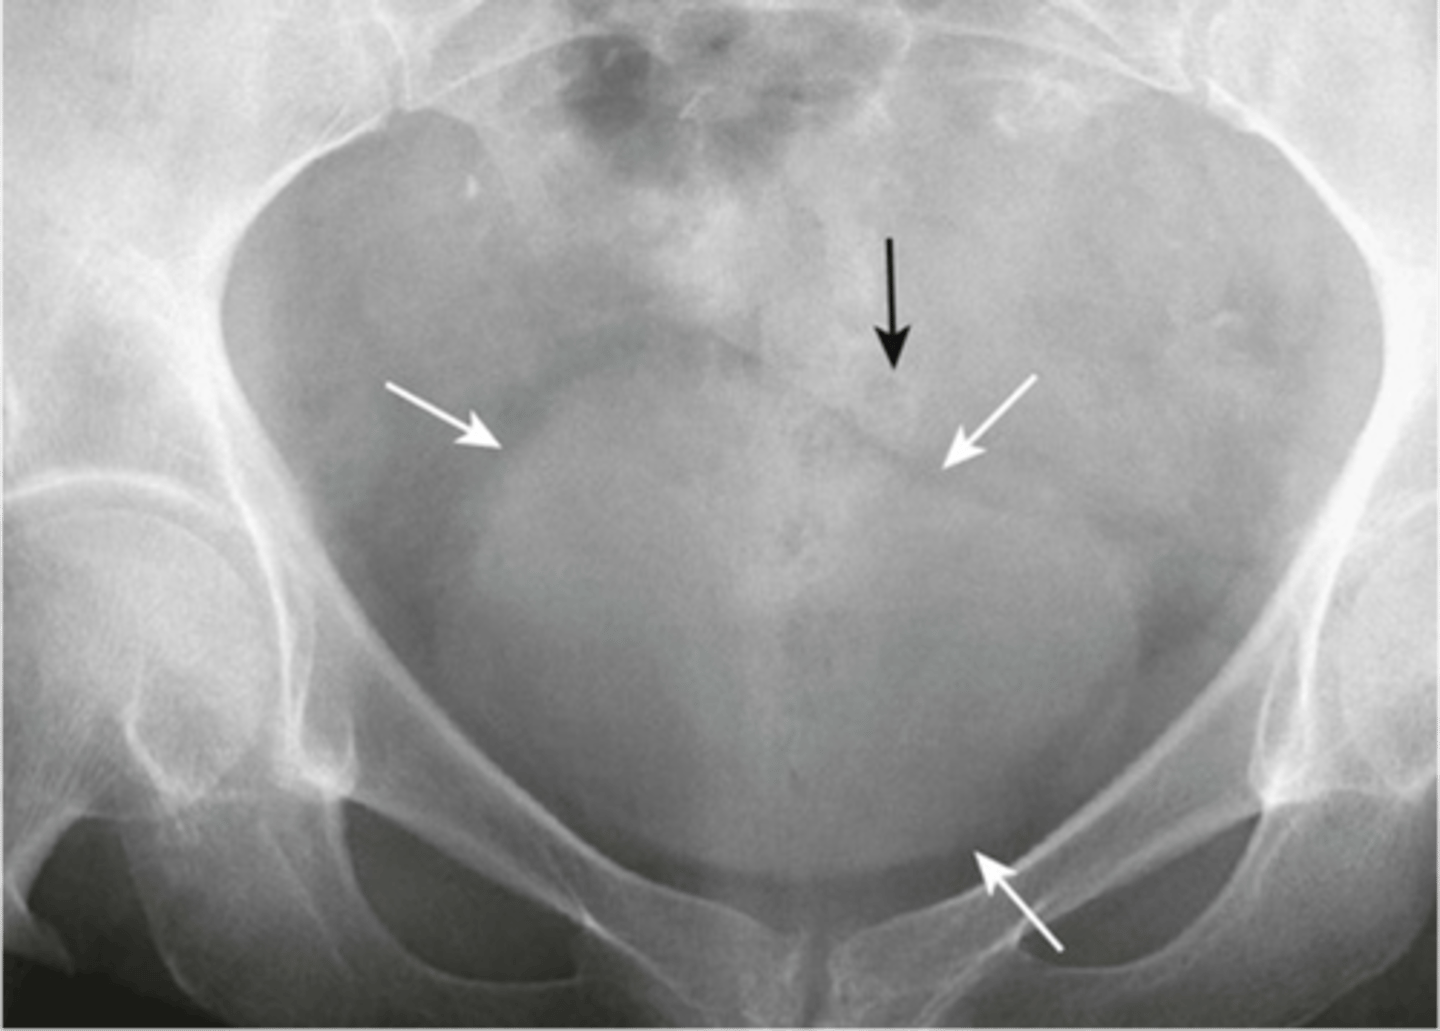

Uterine fibroid/Leiomyoma